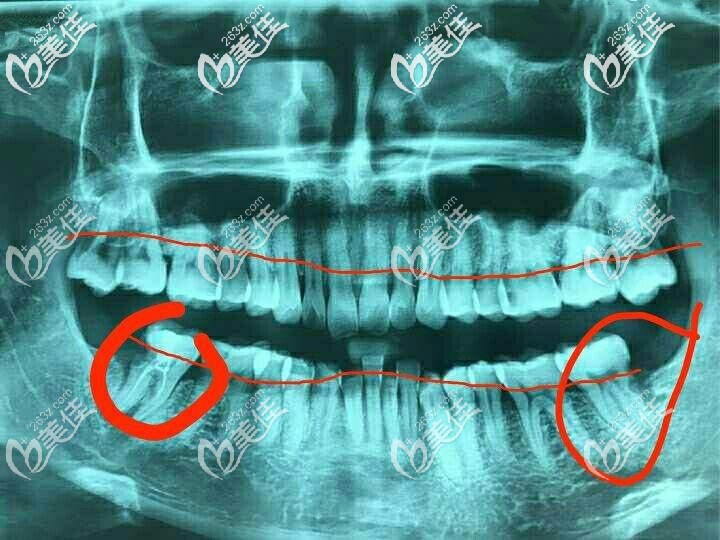

有跟我一樣年紀(jì)輕輕牙槽骨就已經(jīng)吸收三分之一的伙伴嗎?我今年才35歲呀,不知道這種情況還能不能做種植牙了。如果可以的話韓國奧齒泰這個種植體咋樣?聽說性價比挺高的。

牙齒拍片圖

你的牙齒是因為牙周病導(dǎo)致的牙槽骨吸收吧,看你的牙片,牙槽骨吸收的比較厲害,達(dá)到牙根1/3了,是需要先進(jìn)行拔牙治療的。

拔牙之后得先值骨粉,骨粉一般是按克來收費(fèi)的。像0.5g的骨粉一般在3000元左右。骨粉植入牙槽骨后,要等缺損區(qū)骨質(zhì)恢復(fù)正常形態(tài)和功能后才可以做種植牙。

你的年紀(jì)比較小,如果資金充足,建議選擇臨床時間久的種植體,比如瑞士ITI或者德國BEGO這兩款。要是資金有限,奧齒泰也是個不錯的選擇。